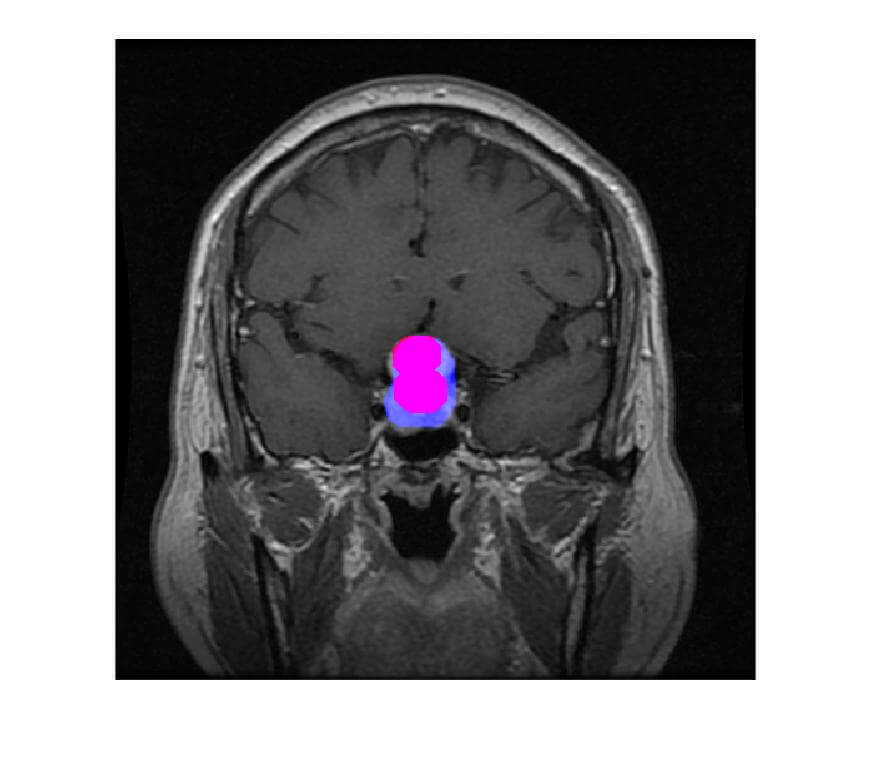

- The extracted tumor will be highlighted in red color and Blue color is the true tumor.